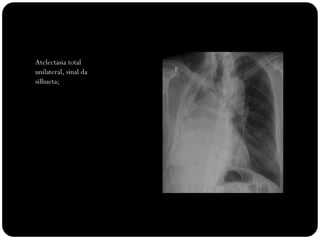

Atelectasia total

unilateral, sinal da

silhueta;

total unilateral